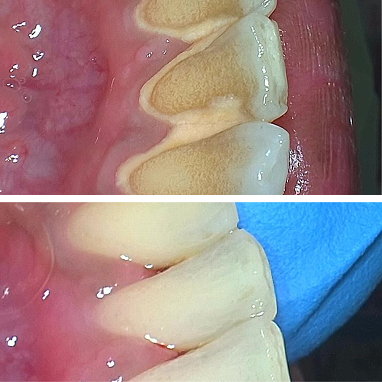

Setiap scaling dilengkapi polishing, membuat gigi lebih halus, bersih, dan tampak cerah setelah perawatan.

Karang gigi dibersihkan menyeluruh, termasuk area sulit dijangkau, sehingga gigi dan gusi tetap sehat lebih lama.

Di Dharmawangsa Dental Studio, scaling sudah termasuk polishing. Hasilnya lebih bersih menyeluruh, bukan sekadar karang gigi terangkat. Jangan tergiur harga murah di luar yang berakhir dengan biaya tambahan.